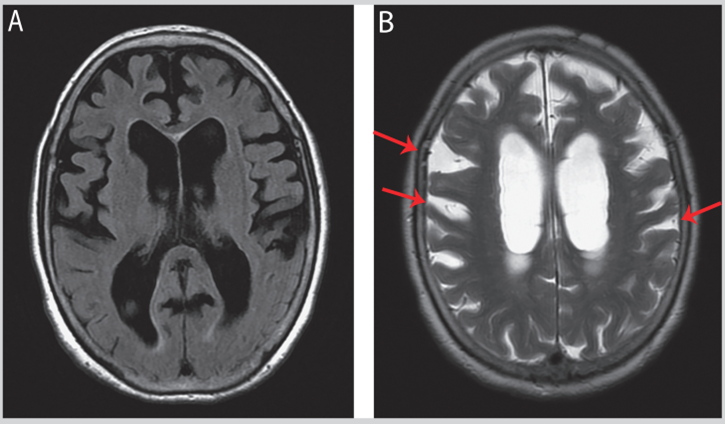

临床上看到的额叶脑沟增宽,看似是脑萎缩,但结合临床症状和影像特征需考虑HS,如图3。

图3:患者的MRI(横轴位)Evans指数为0.40,B显示大脑凸面上方的脑沟明显增宽,不成比例的蛛网膜下腔扩大(DESH)(图源:参考文献[2])

蛛网膜下腔扩大+脑室成比例扩大是脑萎缩的典型影像学特征(图4A)。脑室异常扩大,但蛛网膜下腔未被挤压变窄是慢性梗阻性脑积水的特征(图4B)4。

图4A:脑萎缩:箭头所示的蛛网膜下腔扩大,与脑室扩大(脑室增宽)的程度是成比例的。B:慢性梗阻性脑积水:星号所示的脑室显著扩大,但箭头所示的顶部及内侧蛛网膜下腔仍处于开放/未受压状态(图源:参考文献[4])